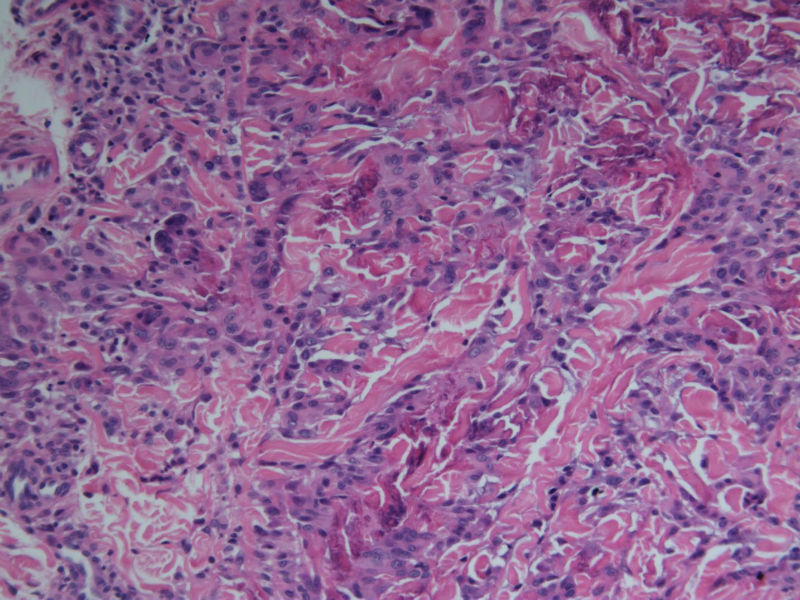

患者 男,8岁,双小腿渐粗红肿伴痒20余天,皮疹渐扩大,且出现硬化萎缩,入院后发现肺吸虫(+)。临床考虑:肺吸虫病硬皮病。请问斑竹大人考虑啥?

• 双小腿红肿伴痒20余天图4

图4

肺吸虫引起的嗜酸性粒细胞增多性疾病

肉芽肿中央不是凝固性坏死,好像是胶原纤维,否为环状肉芽肿或类脂质渐进性坏死

要考虑Wells综合征,依据有肺吸虫检查阳性、皮疹表现为肉芽肿样表现,可见到火焰征,不知道临床上血液分析检查结果如何,以及其他的检查结果怎么样?

肺吸虫皮下结节表现为肉芽肿炎症,这里的图片所显示的就是真皮及皮下组织的肉芽肿炎症,若是肺吸虫所致,按理是多少能见到嗜酸粒细胞的,但这里确实是没有看到,也没见可以的虫体征象,是没切到?也似乎没见很明显的硬皮病相关表现。

补充(临床医生邮件提供)该病人是一个8岁的小男孩,此次就诊主因双小腿肿胀发硬伴痒20天入院。既往体健,无内脏疾病史,入院时无发热、咳嗽、咳痰,无腹痛、腹泻等不适。专科检查:双小腿弥漫肿胀性褐色斑块,皮疹边界清楚,左小腿较右小腿肿胀明显,左小腿皮肤弹性较正常差,皮温正常,皮肤表面未见抓痕,未见红斑、丘疹、结节等,未见糜烂、破溃。入院查血分析嗜酸性粒细胞百分之六十多,余未见明显异常;体液免疫是IgE升高明显,有一百多倍吧,具体记不清。行肺吸虫皮试阳性,胸部CT及全腹CT检查均可见感染性病变,颅脑CT未见异常。给予杀虫治疗1疗程后,左小腿肿胀明显消退,现两小腿粗细相当,左小腿肿胀发硬也明显缓解,但褐色色沉一直未见明显消退,而且还向大腿蔓延,未见明显肿胀发硬的改变。患者现无瘙痒、肿胀感等不适。患者皮疹并不是肺吸虫病的典型皮疹,故行病理检查明确皮疹是否于肺吸虫病相关。

谢谢!开了眼界了!再次细看病理图,那些类似于“火焰征”的还真是像脱颗粒的嗜酸粒细胞,只是显而易见的嗜酸粒细胞不多见。末梢血嗜酸粒细胞那么多···推想皮疹应该是和肺吸虫有关,只是我们这辈的没啥见过、也很难见到了,还请前辈多多指点啊!

1、患者的皮损与血液中嗜酸性粒细胞增多有关,病理改变的确类似Wells综合征的灶状坏死,但没有特异性。

2、嗜酸性粒细胞增多可以表现为毛囊炎,蜂窝织炎,脂膜炎,筋膜炎,嗜酸性皮病和增多综合征等,

3、其产生的原因常常是寄生虫,此例明确有肺吸虫。所以两者有明确的相关性。